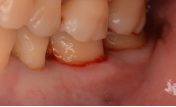

牙石堆积                                         牙龈红肿出血